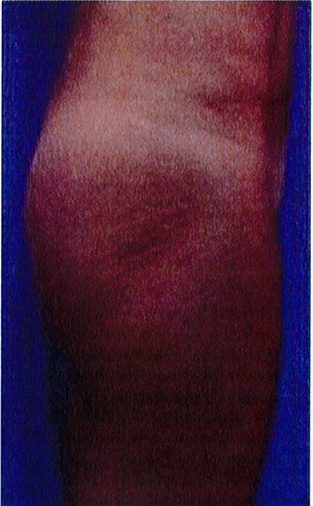

Bệnh nhân 52 tuổi xuất hiện chùng da vùng mông (mức độ nặng), mong muốn giải quyết vấn đề này đồng thời tăng kích thước vòng ba. Hai khối anatomic implant

Hình. 19. . (A) Hình anh trước và (B) và sau phẫu thuật làm đầy mông của bệnh nhân chùng da vùng mông tương đối nhiều. Bệnh nhân được đặt khối implant dưới cân thể tích 330 mL ở hai bên.

thể tích 330mL dạng silicone được đặt ở dưới cân cơ mông lớn.Hậu phẫu đánh giá thấy giảm thời gian hồi phục (Hình 19).